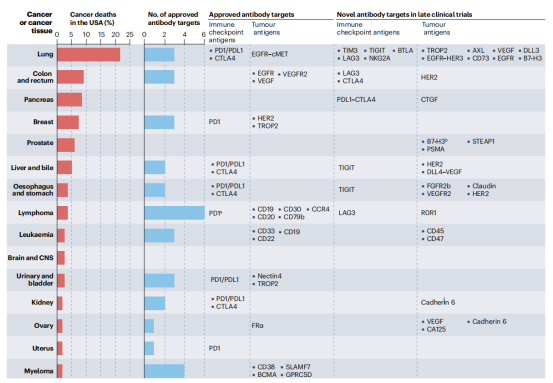

免疫检查点抑制剂:针对免疫细胞调节检查点的单特异性抗体在癌症患者中显示出了显著的临床疗效。FDA和EMA批准的11种免疫检查点抑制抗体目前正在用于治疗20多种不同类型的癌症,包括肺癌、黑色素瘤、肾细胞癌、头颈部鳞状细胞癌,预计还有几种这些抑制性抗体将在不久的将来获得批准。

肿瘤药物开发是一个艰巨的过程,成功率为3%,具体到肿瘤领域,目前缺乏基于抗体的治疗方法的成功率数据,约18%的治疗性抗体进入I期试验后进入药物上市。这些低数字反映了药物开发过程中遇到的许多障碍。与血液系统恶性肿瘤相比,实体瘤的抗体发展滞后,主要是因为缺乏可靶向抗原。不同的淋巴瘤亚型占所有癌症死亡的约3%,有5种肿瘤抗原(CD19、CD20、CD79b、CD30、CCR4和PD1)被治疗性抗体靶向。相比之下,占癌症死亡人数约21%的肺癌只有一种可靶向肿瘤抗原(EGFR-MET)。

免疫检查点抑制剂在靶向治疗中发挥重要作用,FDA和EMA已经批准了11种不同版本的CTLA4、PD1和PDL1靶向抗体,用于超过20种癌症的65种不同适应症。但是目前的免疫检查点抑制剂会引起一些并发症,其中大概1%是致命的,40%具有慢性毒性,我们应该优先考虑新的免疫检查点调节剂的基础和转化研究,如B细胞和T淋巴细胞衰减剂(BTLA)。